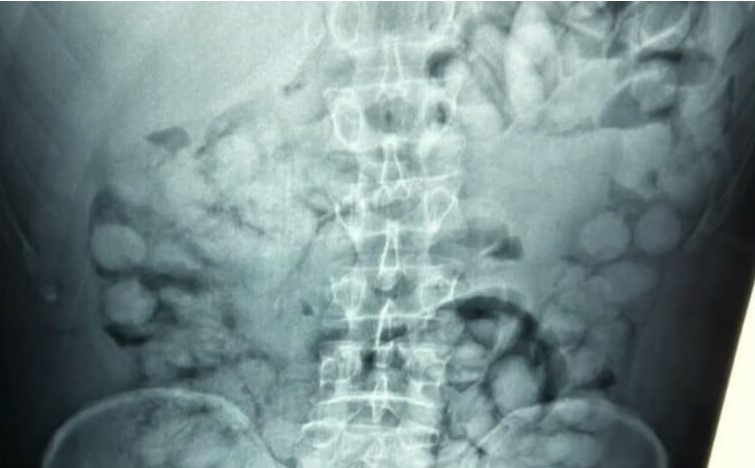

Κατά τον έλεγχο, οι αστυνομικοί εντόπισαν ύποπτα ευρήματα και ο άνδρας οδηγήθηκε άμεσα για ιατρικές εξετάσεις. Η ακτινογραφία που ακολούθησε αποκάλυψε πως είχε καταπιεί 100 κάψουλες κοκαΐνης, βάρους περίπου 11 γραμμαρίων η καθεμία.

Η συνολική ποσότητα του ναρκωτικού που κατασχέθηκε ξεπερνά το ένα κιλό, ενώ οι κάψουλες έφεραν ειδική επικάλυψη για να αντέξουν στο πεπτικό σύστημα.

Η Ελληνική Αστυνομία έδωσε στη δημοσιότητα χαρακτηριστικές εικόνες από τις ακτινογραφίες, ενώ η έρευνα συνεχίζεται για τον εντοπισμό πιθανών συνεργών του συλληφθέντος.